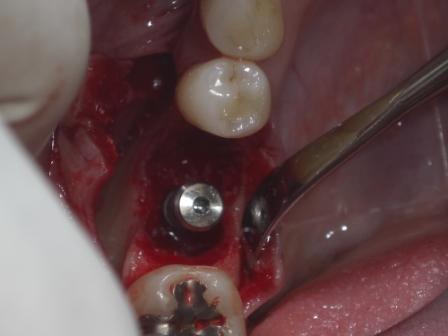

昨日のオペは午前中サイナス+GTR、午後インプラントのオペがありました。

そして午後は大幅に骨欠損している場所に埋入、ボーンスクレイパーで自家骨を採取してGBRを行いました。